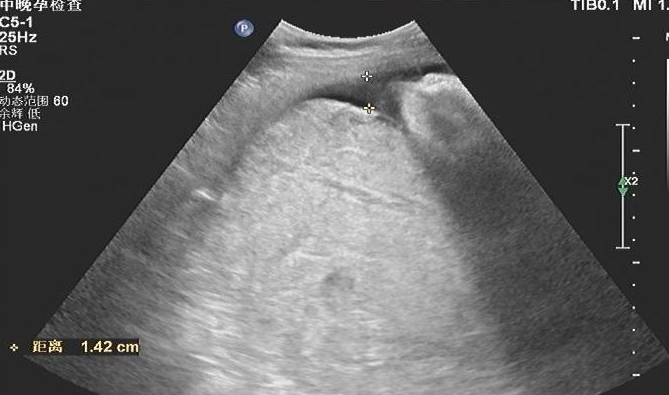

典型的胎盘早剥超声表现:超声表现为胎盘明显增厚,胎盘实质回声不均匀,胎盘血肿为增厚的胎盘实质内或后方见混合回声包块。

不典型的胎盘早剥超声表现:(1)胎盘与宫壁间较小的圆形低、无回声,甚至在胎盘与宫壁间仅见窄带状、眉笔样低无回声,与宫壁分界欠清晰;(2)胎盘仅局部增厚,内部回声均匀;(3)胎盘弥漫性增厚,回声均匀增强,与肌壁间未见异常回声。